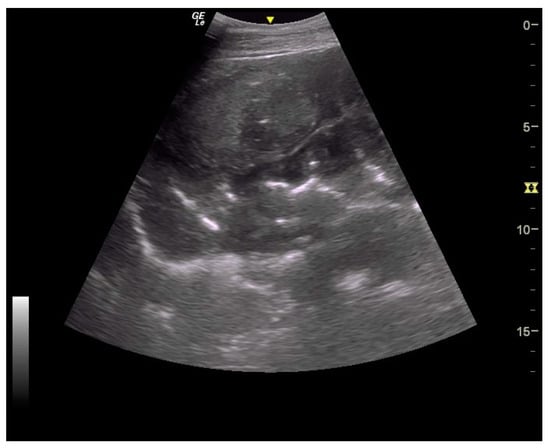

Figure 7.

Ultrasound images of large colon. Very severe thickening of large colon.

Thickening of the colon wall was significantly greater (p = 0.02) among the horses which did not survive (36 ± 19 mm versus 19 ± 6 mm) (Figure 5). Beyond 22 mm of thickness, the horses presenting such damages of the colon had significantly (p = 0.01) lower chances of survive with a positive predictive value of non-survival of 89% (Table 1). Thickening of the small intestine was observed for 35% (6/17) of the horses on which ultrasonography was performed. Abdominal ultrasonography showed severe thickening of the colon wall with values rarely encountered in other diseases with an average of 29 ± 17 mm (Figure 6 and Figure 7).

In addition to the marked seasonality, the clinical presentation was quite typical with an acute to fulminant severe edematous colitis leading to toxic shock, which was complicated in several cases with marked azotemia, increase hepatic or muscle enzymes, and intravascular hemolysis. Although not fully detailed in other studies, the hemato-biochemical results were similar to previous reports [,] and can be easily understood in view of the acute colitis shock. Abdominal ultrasonography examination revealed marked thickening of the large colon wall, especially in non-survivors with values rarely encountered in other diseases. The thickness was so severe that clear measurement was sometimes difficult (Figure 7). This reflects the severe colon edema as it could be observed post-mortem (Figure 11 and Figure 12).